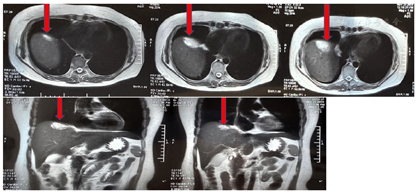

腹盆增强核磁(2018年6月28日北医三院)示:肝占位病变,考虑肝转移(图2)。